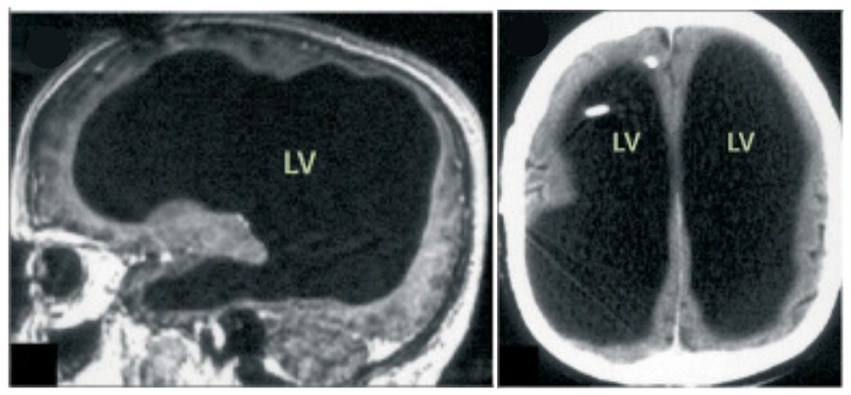

Then, in 2007, in Marseille, France, a 44-year-old man complaining of weakness in his left leg submitted to an MRI brain scan (Feuillet et al., 2007). As Figure 5 shows, the skull was abnormally filled with cerebrospinal fluid, leaving only a thin sheet of actual brain tissue. As an infant, he’d had a shunt inserted into his head to drain the fluid but it was removed when he was 14. Evidently, the cerebrospinal fluid build-up did not stop and ended up reducing the brain’s size to 50–75% compared to its normal volume. Though he had a below-average IQ (75/100), this man had a job, a family, and a normal life.

Figure 5

MRI image of a hydrocephalus brain. Credit: Feuillet et al. (2007). Copyright 2022, reproduced with permission from Elsevier.